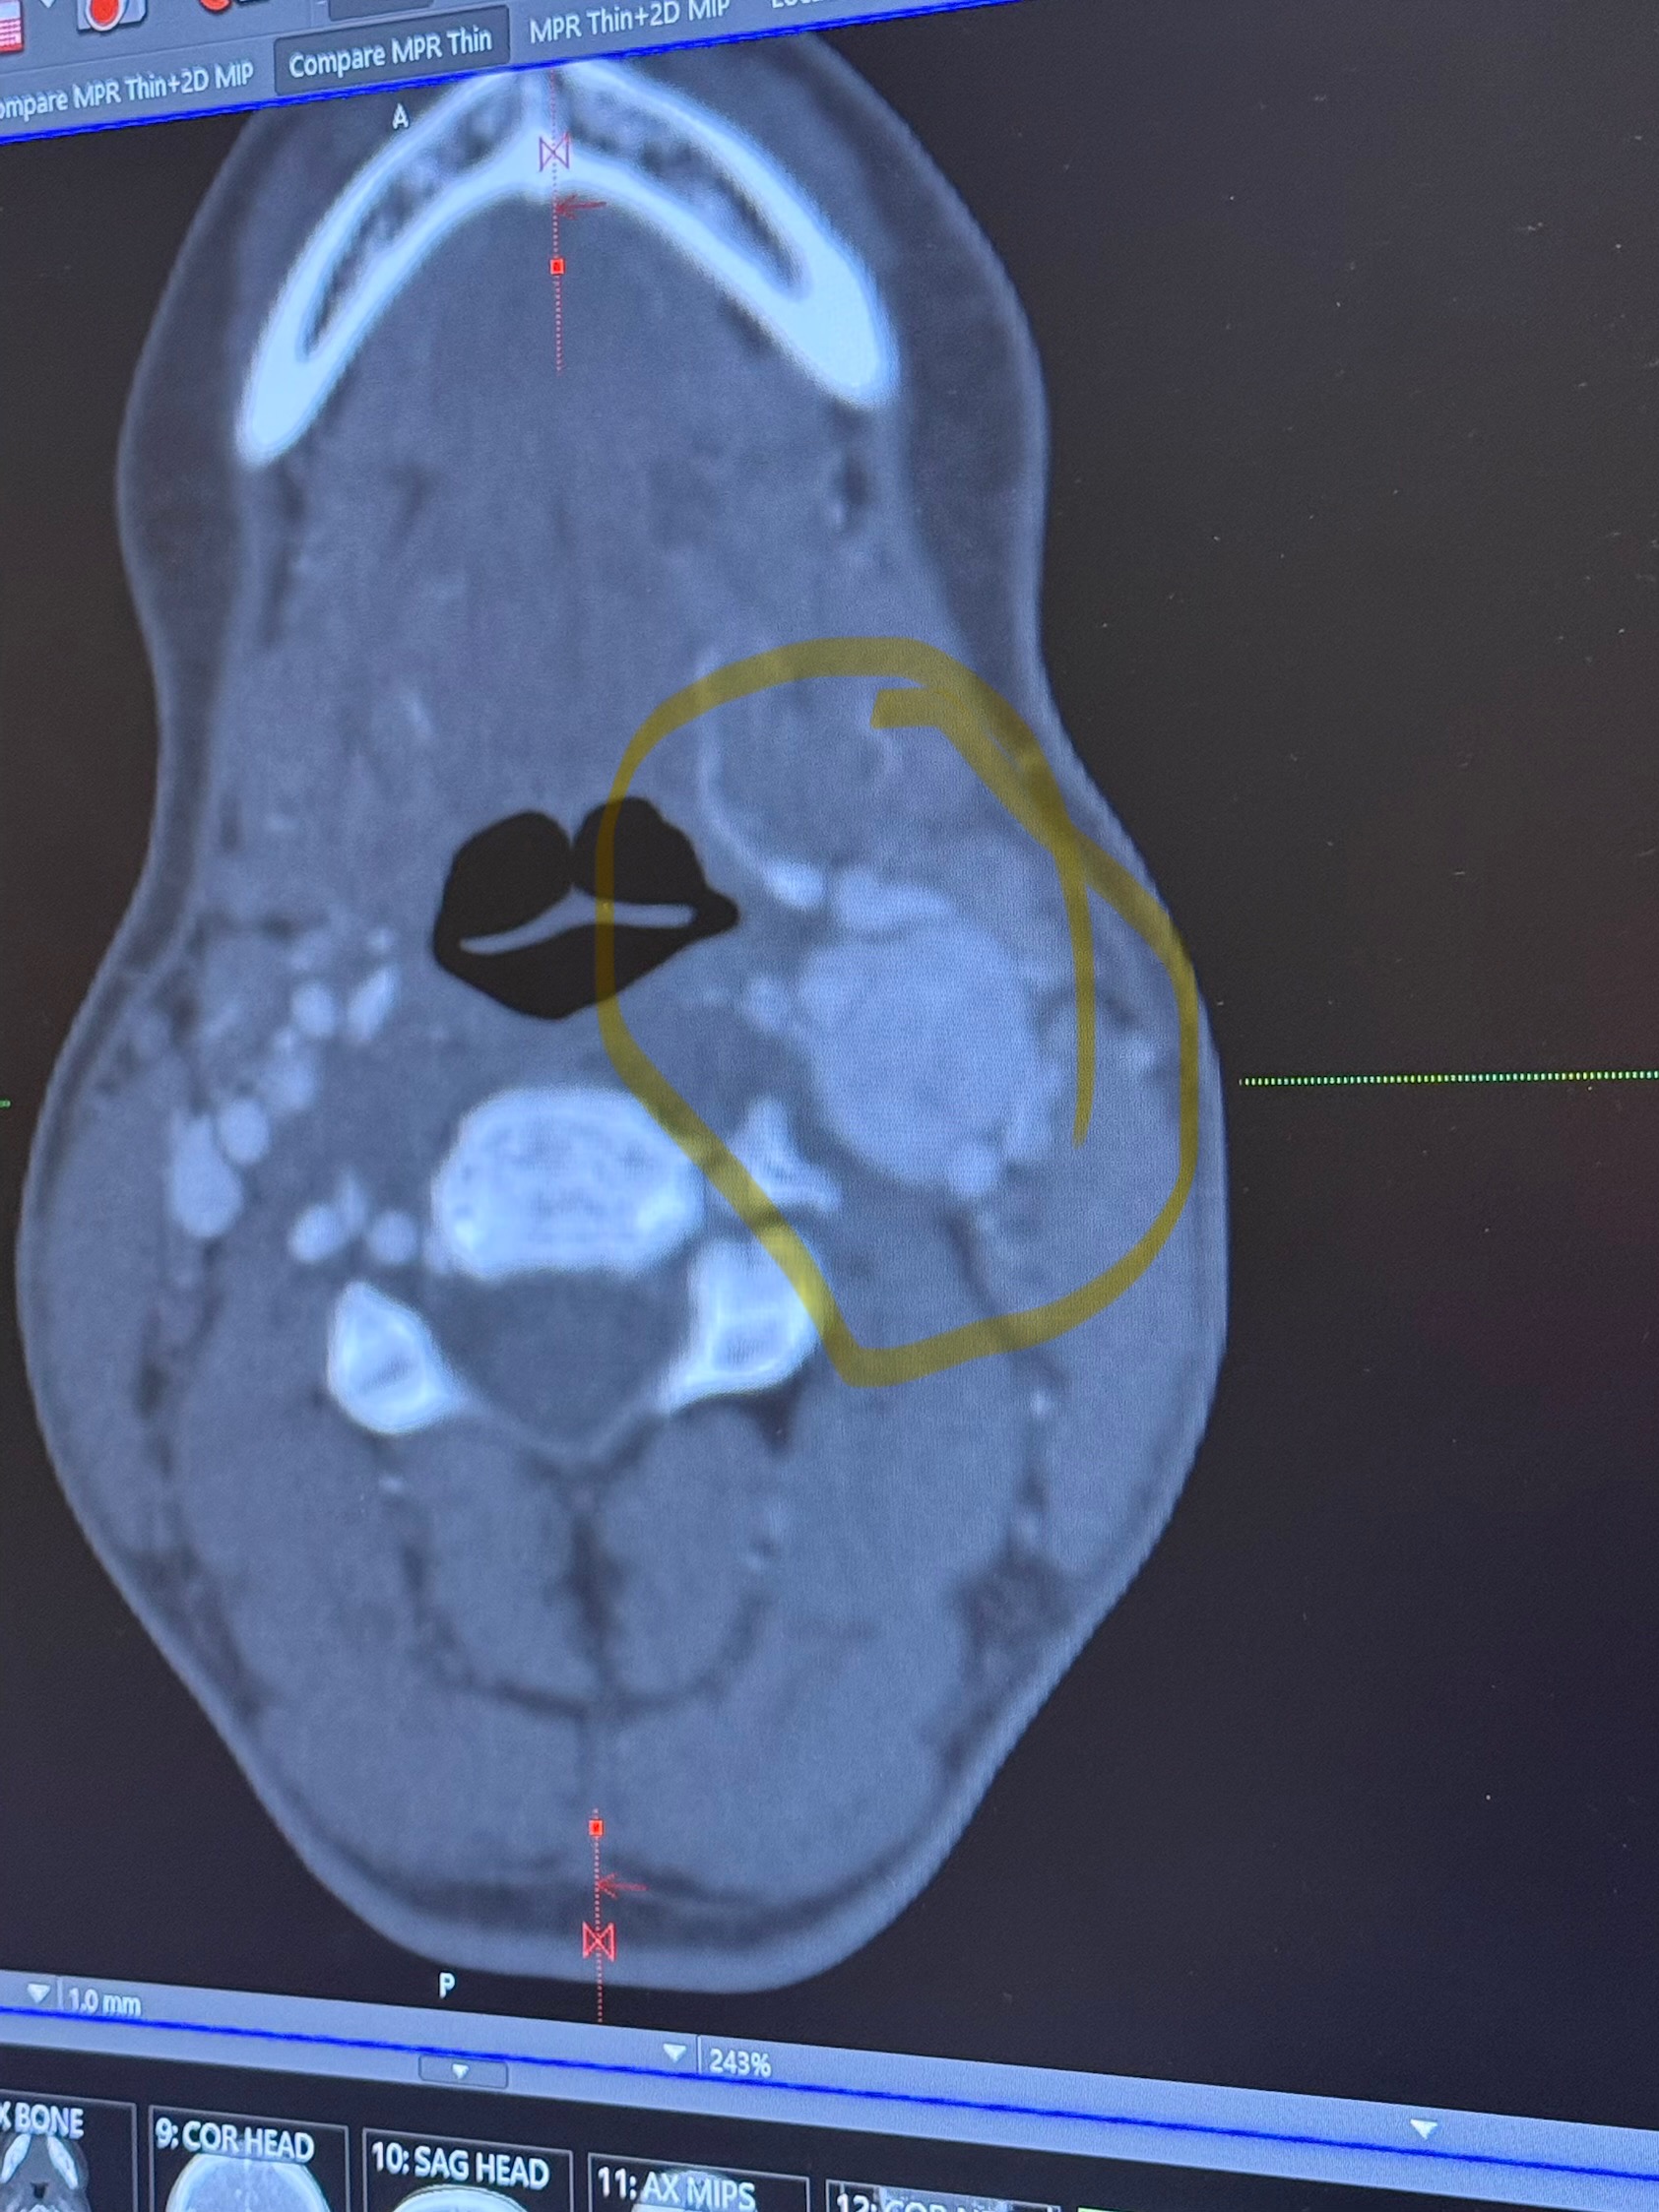

It's been there for years, specifically the last couple of years growing much larger.

You can see in the CT scan the size.